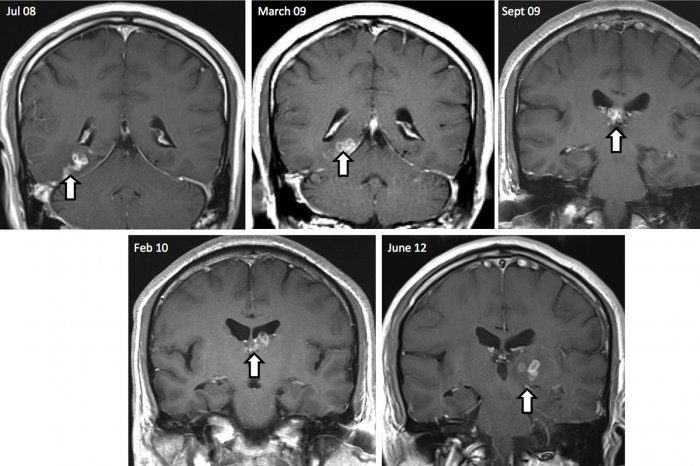

все спрашивают: как? да откуда?

я другой вопрос подниму: снимки датированы 12-м, 10-м, 9-м и 8-м годами.

не прошло и четыре года, как говорится.

они снимки эти делают чтобы с умным видом около них постоять? или взять баблосов побольше "за лечение"?

судя по фото, этого червя видно неплохо. а обнаружили его "случайно".